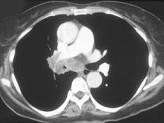

问题 男,56岁,咳嗽,咯血1月余,有吸烟史30余年,结合CT检查图,选出最可能的诊断 ( )

选项 A.肺结核 B.肺炎 C.结节病 D.肺错构瘤 E.中央型肺癌

答案 E